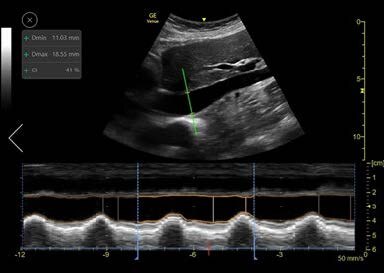

Once the longitudinal view is acquired and the Auto IVC tool is activated, the system automatically locates the IVC and places an AMM cursor through it. The cursor tracks the longitudinal location within the IVC and the AMM automatically adjusts its tilt to maintain perpendicular incidence to the IVC. The user may tap on the image while scanning to choose a different location for the AMM as desired. The Auto IVC tool measures the maximum and minimum diameters of the IVC throughout the respirator cycles in real-time. The AMM timeline traces the diameter of the IVC over time and the collapsibility or distensibility index results are displayed in the measurements result window. Linear graphics on the AMM timeline indicate the minimum and maximum diameters and the user can readjust their positions, if desired, based on clinical judgement.

By default, the timeline is divided into time intervals of 4 seconds each. This is defined as the Calculation Time Interval, or CTI. Results appear in the Results Window for the selected interval. By default, the last complete CTI is selected. If required, the user can select a different CTI. The borders of each CTI are marked by dotted lines. Calculations are done in real time and the results are displayed in the results box upon completion of each respiratory cycle. The image is stored, and the results are saved in the measurements report.

Figure 2: Auto IVC Tool Screen layout